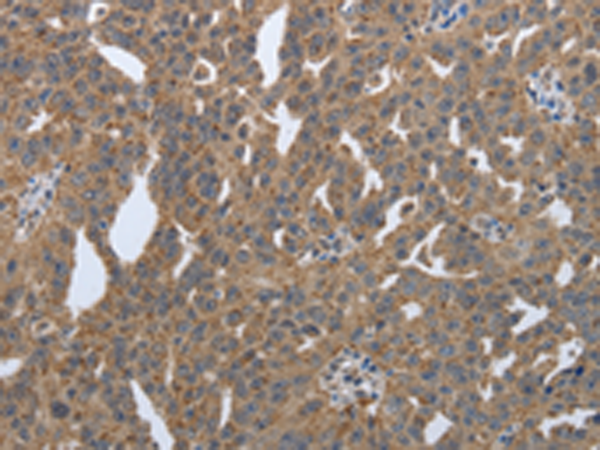

分类: 科研抗体货号: P11315别名: PDI, PDA2, PDIP, PDIR应用: IHC反应种属: Human